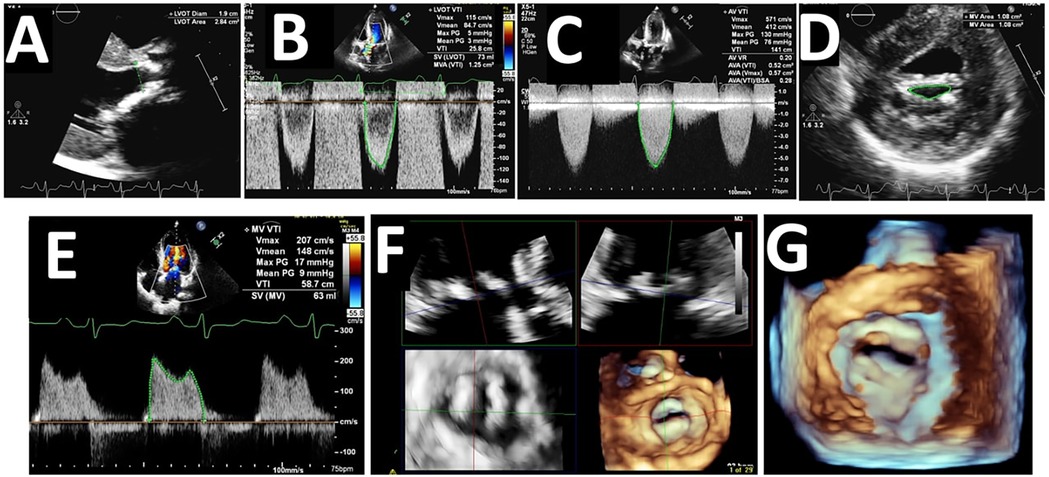

The stroke volume index was 43 ± 11 ml/m2 in the whole cohort without significant differences between the two groups. Moreover, the percentage of those with “paradoxical” low stroke indexed < 35 ml/m2 was 24% in the whole cohort and was not higher in the group with associated MS (p = 0.52). Lastly, no difference was observed in the transvalvular flow rate between the two groups (p = 0.89). A representative echocardiographic case of concomitant AS-MS is shown in Figure 2.

Figure 2. Echocardiographic findings in a patient with concomitant aortic stenosis and mitral stenosis. (A) Parasternal long-axis view showing the left ventricular outflow tract (LVOT) diameter (1.9 cm) and area (2.84 cm2); (B) Pulse-wave Doppler tracing at the LVOT showing velocity-time integral (VTI) of 25.8 cm and calculated stroke volume (SV) of 73 ml, with a mitral valve area (MVA) of 1.25 cm2 derived from VTI; (C) Continuous-wave Doppler tracing across the aortic valve showing a peak velocity of 571 cm/s and mean gradient of 76 mmHg, with a calculated aortic valve area of 0.57 cm2, indicating severe AS; (D) 2D parasternal short-axis view of the mitral valve showing MVA by planimetry (1.08 cm2), consistent with severe MS; (E) Continuous-wave Doppler of the mitral valve showing peak velocity of 207 cm/s and mean transmitral gradient of 9 mmHg, further confirming MS severity; (F) 3D echocardiographic multiplanar reconstruction of the mitral valve, allowing detailed anatomical evaluation of leaflet fusion and valve morphology; (G): 3D-rendered image of the mitral valve orifice, showing the restricted valve opening and commissural fusion in severe MS.